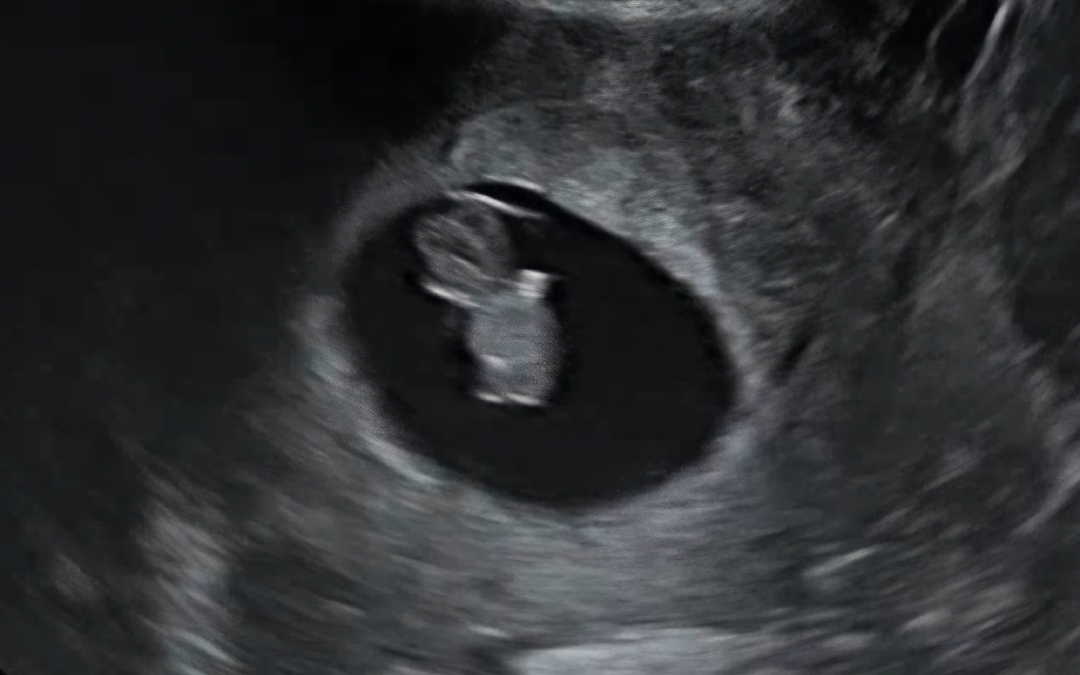

젤리곰 보고 왔어요

꼬물거리는 모습이 너무 사랑스러워서 다같이 보려고 올려봐요♡ 무사히 두 번째 검진 잘 받고 왔습니다😍😍 심박수도 키도 주수에 잘 맞고, 예정일도 변동 없이 이상 무 입니다🩷🩷

저 8주 3일에 보고 왔어요! 초음파 상에서 보이는 각도에 따라 모양이 젤리곰처럼 보이지 않을 수도 있다고 하시더라구요ㅠㅠ!!